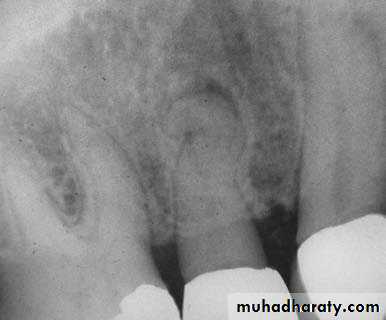

*The No. and curvature of root canals may need modification of outline form & to avoid scarifying of tooth structure.2.Preoperative radiograph: Give great information about status, shape and size of pulp chamber.

Radiographs in Endodontics*Initial radiograph: Diagnosis. *Working length film: Used to determine the length of the canal. *Final instrumentation film: Taken with the final size files in all canals. *Root canal completion film: Taken after the tooth as been temporized. *Recall films: Taken at evaluations.

Requirements of Endodontic Films *Show 4-5 mm beyond the apex of the tooth and the surrounding bone or pathologic condition. *Present an accurate image of the tooth without elongation or fore-shortening. *Exhibit good contrast so all pertinent structures are readily identifiable.